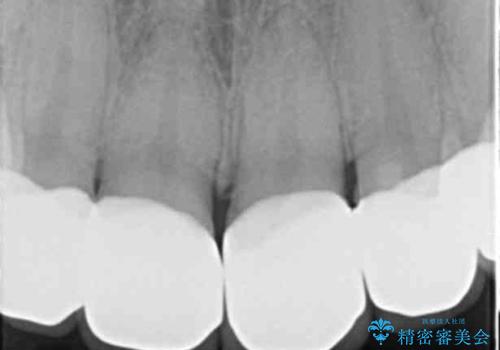

- 保険治療のプラスチックでつぎはぎの歯をセラミックにし、一緒に前歯の並びもきれいにしたいとのご希望でした。

特に裏側のつぎはぎ、二次う蝕(治したところの境目からの虫歯)が多く、審美目的だけでなく、虫歯の治療としても意味があったと思います。

神経を温存するようにあまり削らないように治療しました。